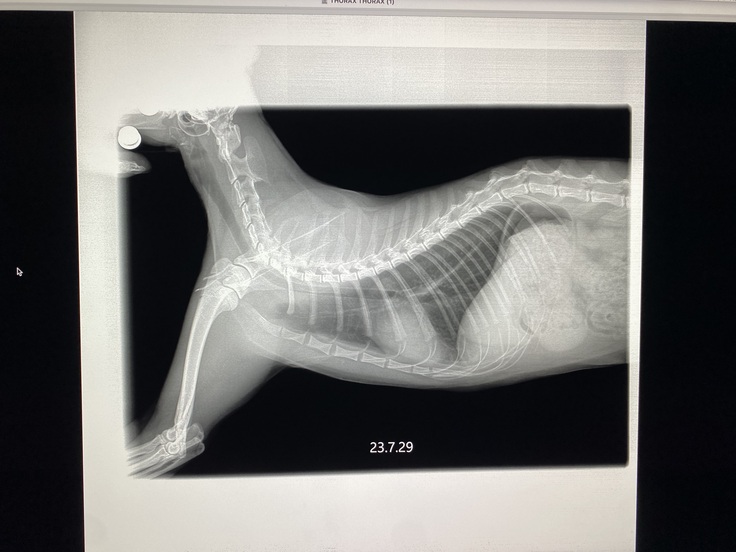

これから、レントゲンやエコー、血液検査です。状態がよければ抗がん剤治療2クールに入ります。獣医師が、私の費用負担を抑えるために毎週レントゲンはやらずに、エコーで頑張って見てくださっていたので、一か月ぶりです。転移はないのか、腫瘍はどうなっているのか、不安です。

レントゲン、血液検査、非常に良好にて、抗がん剤治療2クールめ、スタートです。今日は、ピンクリスチン。昼に治療するので、16時にお迎えします。体重は、先週と変わらず、3.56キロ。食べたのに何故だろう。

胸水も腫瘍もなく、きれいだそうです。